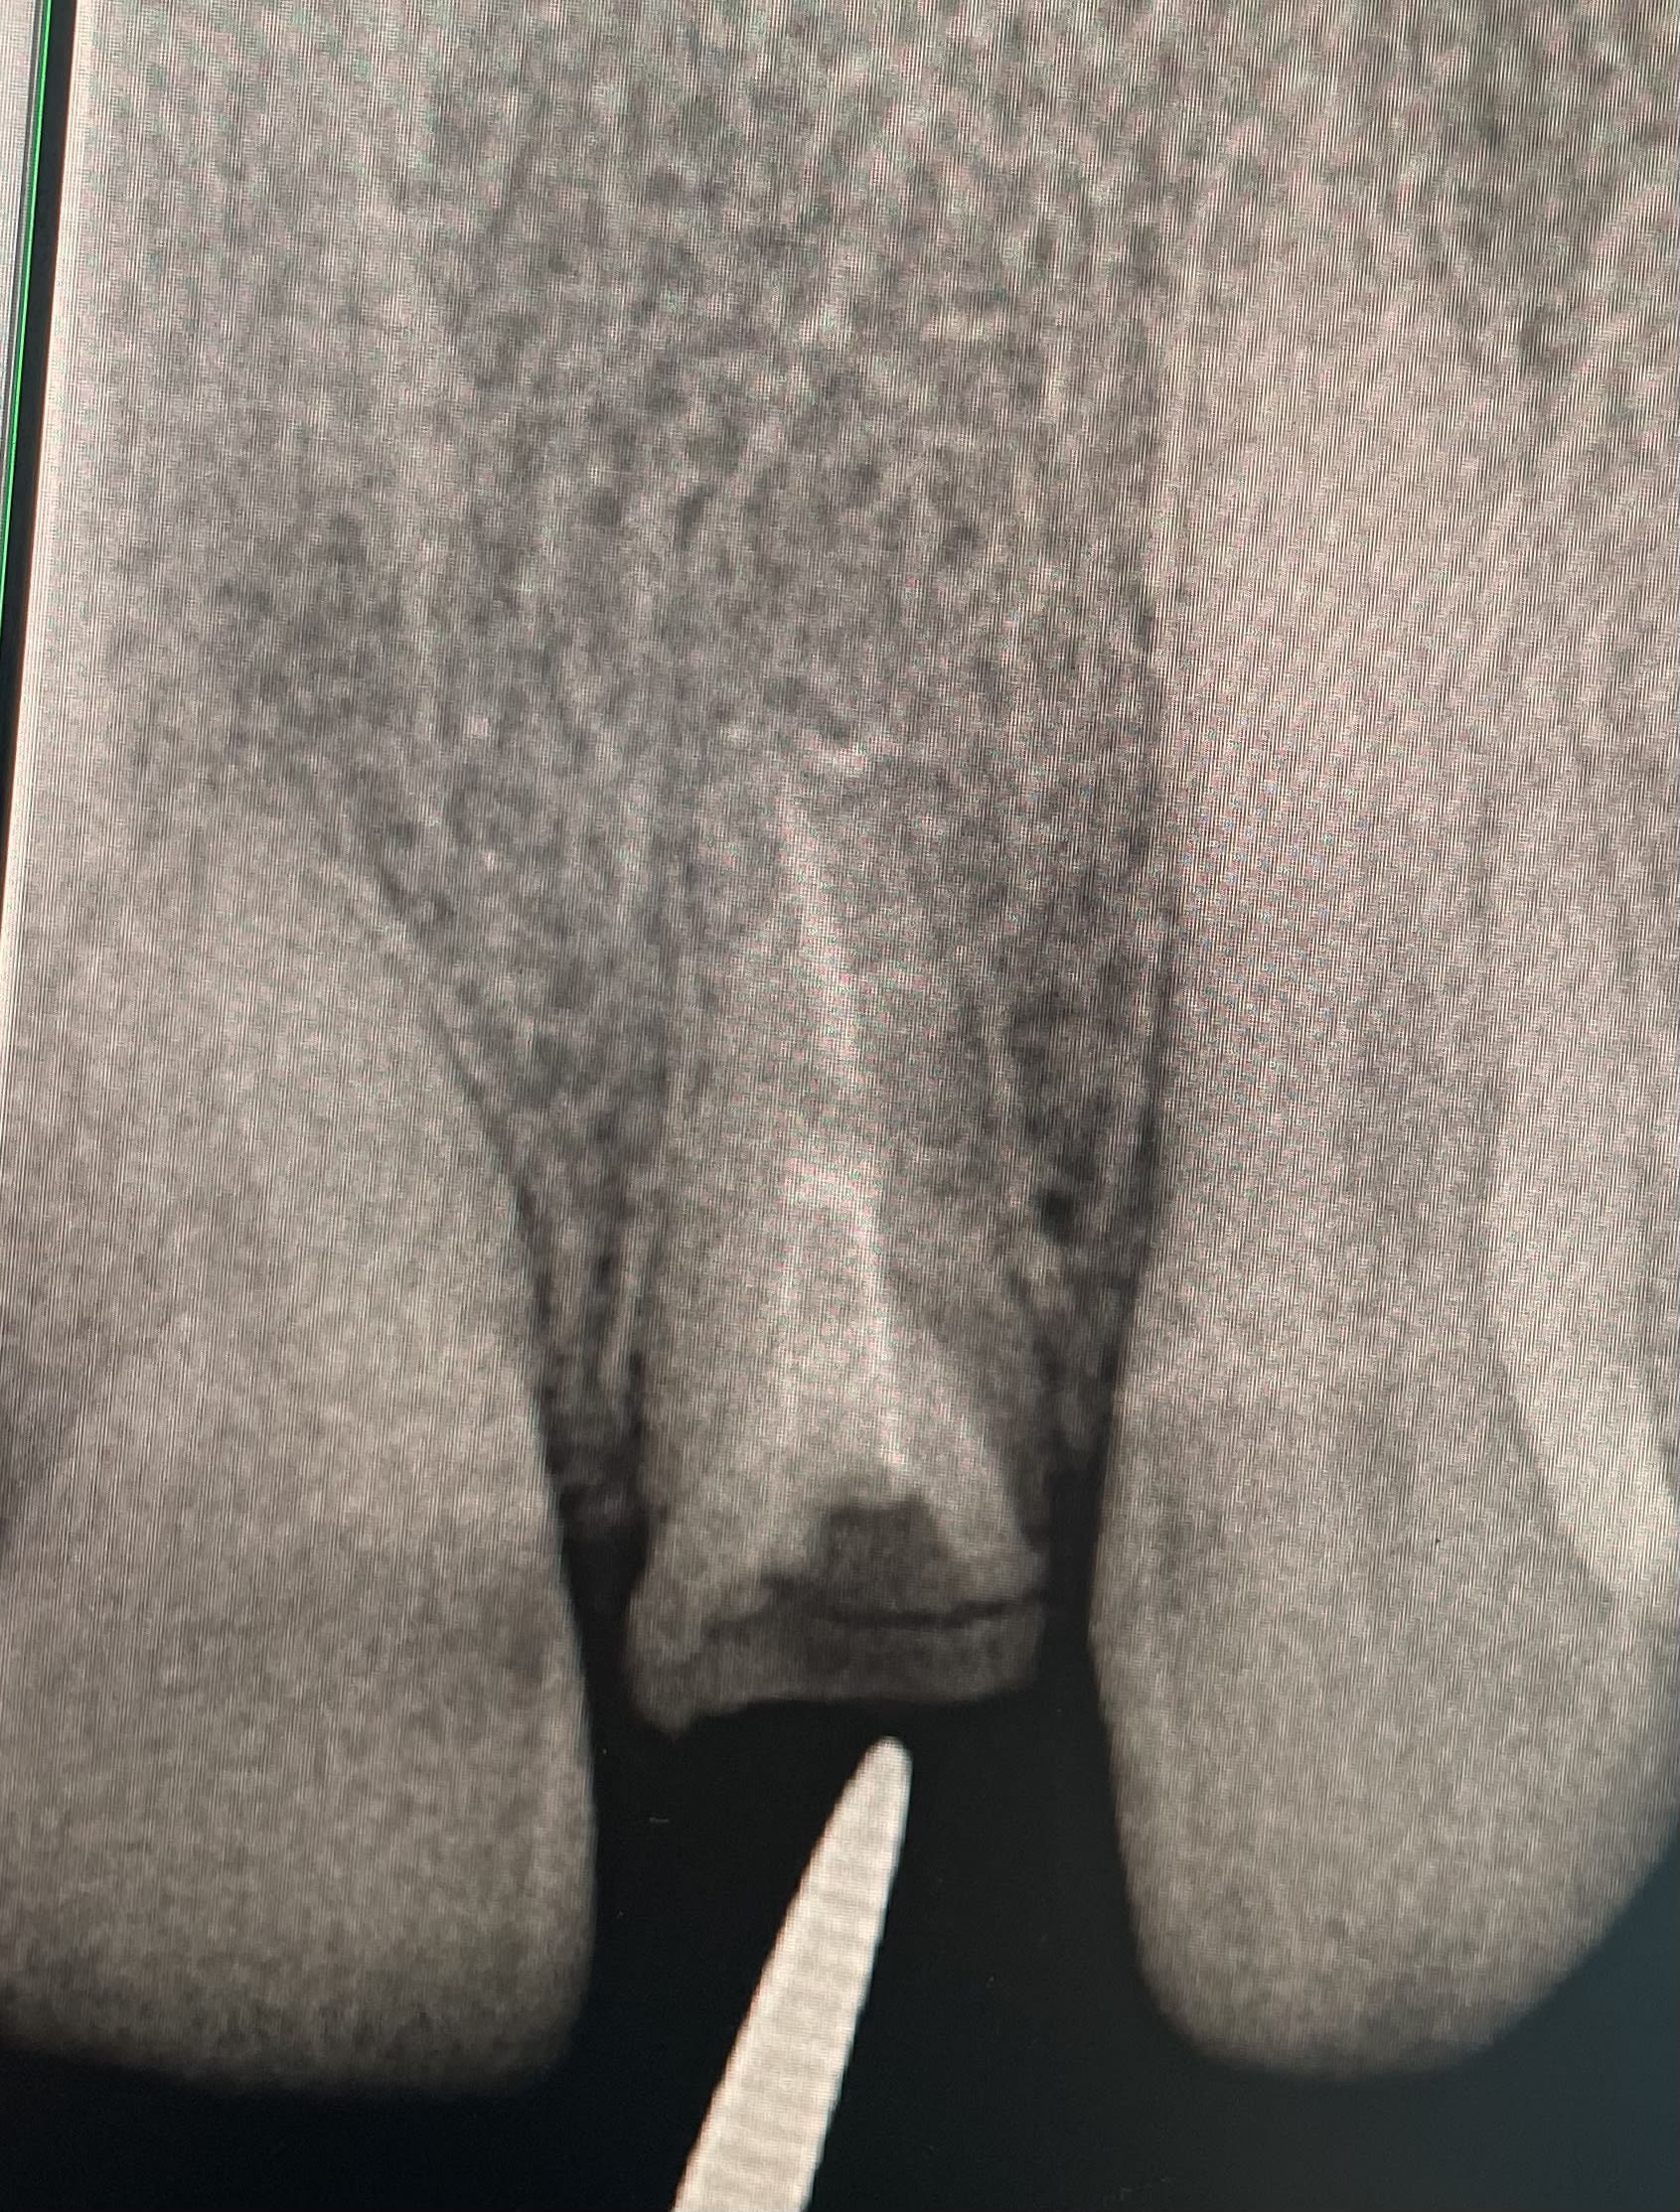

L'usure en palatin des centrales et la fracture sur la racine de la 22 m'interpellent.

Ce serait bien de savoir ce qui se trame à la mandibule pour répondre.

Il y a des facettes d'usures en palatin de la 26 et de la 25.

Du coup il bascule en direction de la 11 et 13. D'ailleurs la 13 quitte le bal

Alors pourquoi la fracture de la 22 ?

La 12 est absente et il est probablement en classe II avec une grosse DDM à la mandibule pour ranger tous le monde en bas.

Peut être une 32 en version qui boxait la 22 à répétition ?